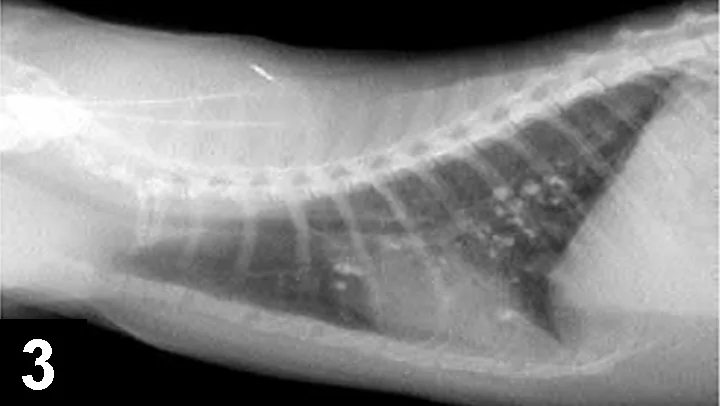

The cat is suspected of having underlying allergic airway disease, although this was not proven. Eosinophils were present in the nasal passages, airways, and blood and are commonly encountered in allergic disease. The mineralized pulmonary nodules seen on thoracic radiographs were thought to be due to dystrophic mineralization of chronically inflamed airways, although granulomas or metastatic disease could not be definitively ruled out.

Interpretation: Multifocal, mineralized, well-circumscribed nodules throughout the lung fields. A diffuse, moderate bronchointerstitial pattern is also present.